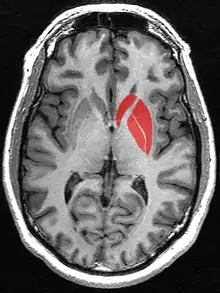

Striatum highlighted in green on coronal T1 MRI images

Striatum highlighted in green on coronal T1 MRI images Striatum highlighted in green on sagittal T1 MRI images

Striatum highlighted in green on sagittal T1 MRI images Striatum highlighted in green on transversal T1 MRI images

Striatum highlighted in green on transversal T1 MRI images